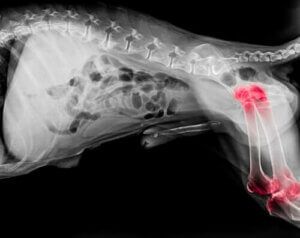

Uzmanlara göre, her beş köpekten birinde kireçlenme durumu görülüyor. Bu eklem problemi her yaşta ortaya çıkabiliyor olsa da, yaşı daha büyük olan köpeklerde çok daha sık ortaya çıkıyor. Genel anlamıyla, artrit, dirsekler ve omuzlardaki eklem yerlerinde iltihaplanmaya sebep olan dejeneratif bir hastalık.

Artrit problemi olan köpeklerin özel bir ilgi ve alakaya ihtiyaçları var. Dejeneratif bir hastalık olduğu için, hafifletici (palyatif) bakım uygulayarak ağrının azaltılması ve öncelikle hastalığın ilerlemesinin durdurulması en iyi yaklaşım yolu olacaktır. Köpeğinizin yaşam kalitesini ortopedik bir yatak almak veya eklem koruyucular kullanmak gibi pek çok yönteme başvurarak artırabilirsiniz. Peki, buna ilave olarak, beslenmesi ile ilgili düzenlemelerle de ona yardımcı olabileceğinizi biliyor muydunuz?